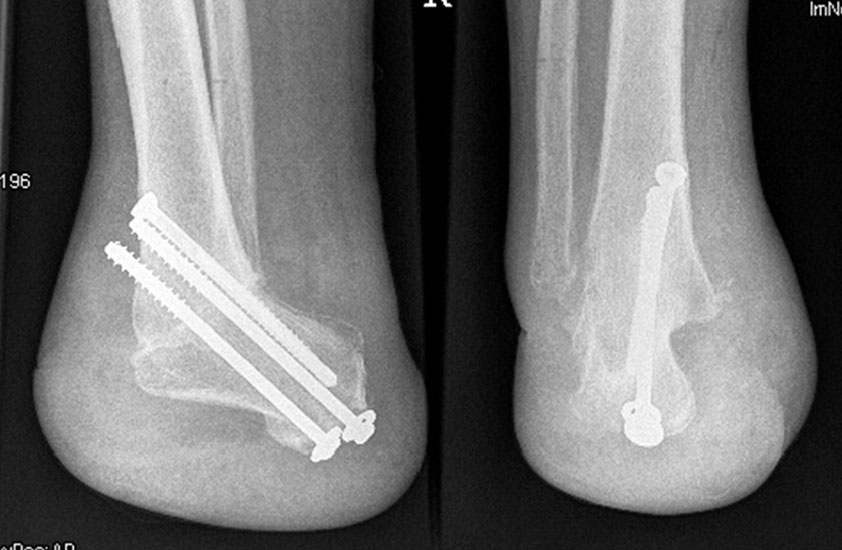

Pirogoff Amputation

Es handelt sich bei der Pirogoffamputation um die Fußamputation unter Belassen des Calcaneus mit anschließender tibiocalcanearer Fusion. Der Stumpf ist „endbelastbar“ mit dem Vorteil gegenüber der Exartikulation im Sprunggelenk (Syme), dass die Beinlänge nur um ca. 2-3 cm verkürzt wird, was das Gehen für kurze Strecke ohne schuhtechnische Hilfe möglich macht. Der Nachteil liegt in Heilungszeit von 6- 8 Wochen bis zur knöchernen Durchbauung und dem Risiko einer Pseudarthrosenentwicklung.

Die Pirogoff-Amputation ist für die Patienten funktionell deutlich günstiger als eine Syme-Amputation.

Operationstechnik

Zur Osteosynthese bevorzugen wir 2-3 kanülierte Großfragmentschrauben (Abb. 49). Postoperativ ist die Extremität für 8 Wochen zu entlasten, wobei zur Sicherheit eine Entlas­tungsorthese verordnet werden kann. Bei schwachen oder unzuverlässigen Patienten empfiehlt es sich, für 8 Wochen einen Ring-Fixateur anzulegen.